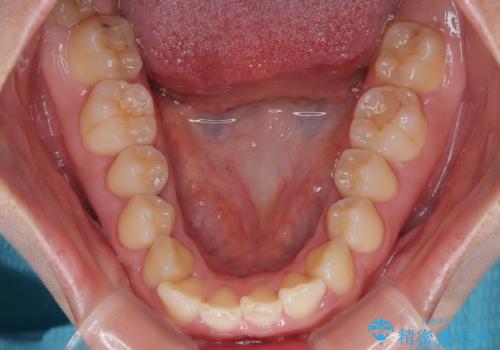

- 前歯のデコボコが気になるでのことで来院された患者様です。

歯列アーチが狭くスペース不足により前歯がデコボコしている状態でした。見た目を改善しつつ、前歯を前方に突出させず、自然な笑顔を目指したいというご希望でした。